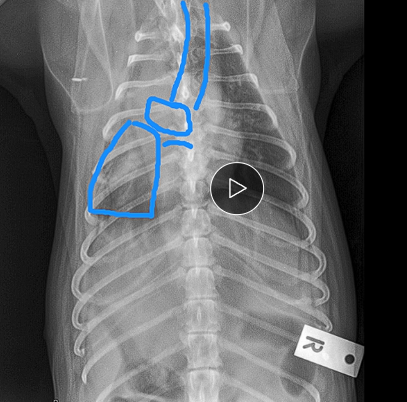

Breed and size predisposition implies genetic component

Weakening of trach rings → trache a collapse → activate mechanoreceptors → dry harsh cough